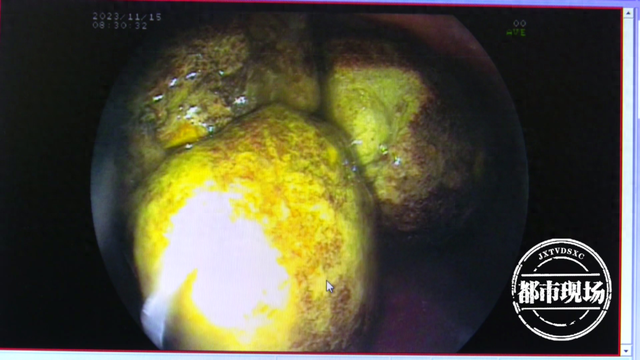

丁先生就医后胃镜检查的图片

图片尺寸640x360